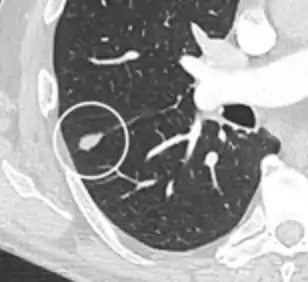

- In case of subsolid nodules, being part solid has a higher risk of cancer than being purely ground glass opacity.

Part solid nodule.[9]

Ground glass opacity nodule.[9]